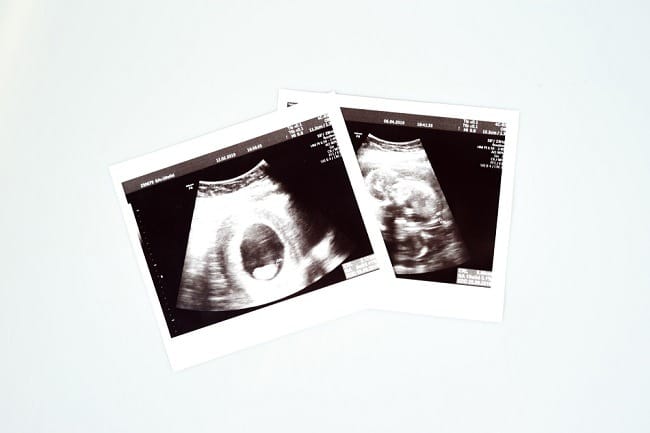

Untuk memeriksa kehamilan, ibu hamil dapat melakukan test pack dan memastikannya melalui USG. Meskipun anatomi janin belum dapat terlihat melalui USG, kantung kehamilan sudah terbentuk di usia kehamilan 7 minggu.

Jantung janin pada usia kehamilan 7 minggu berdetak sekitar 150–180 denyut per menit. Detak jantung ini dapat didengar melalui pemeriksaan USG kehamilan dan dapat menjadi salah satu tanda janin berkembang dengan baik.